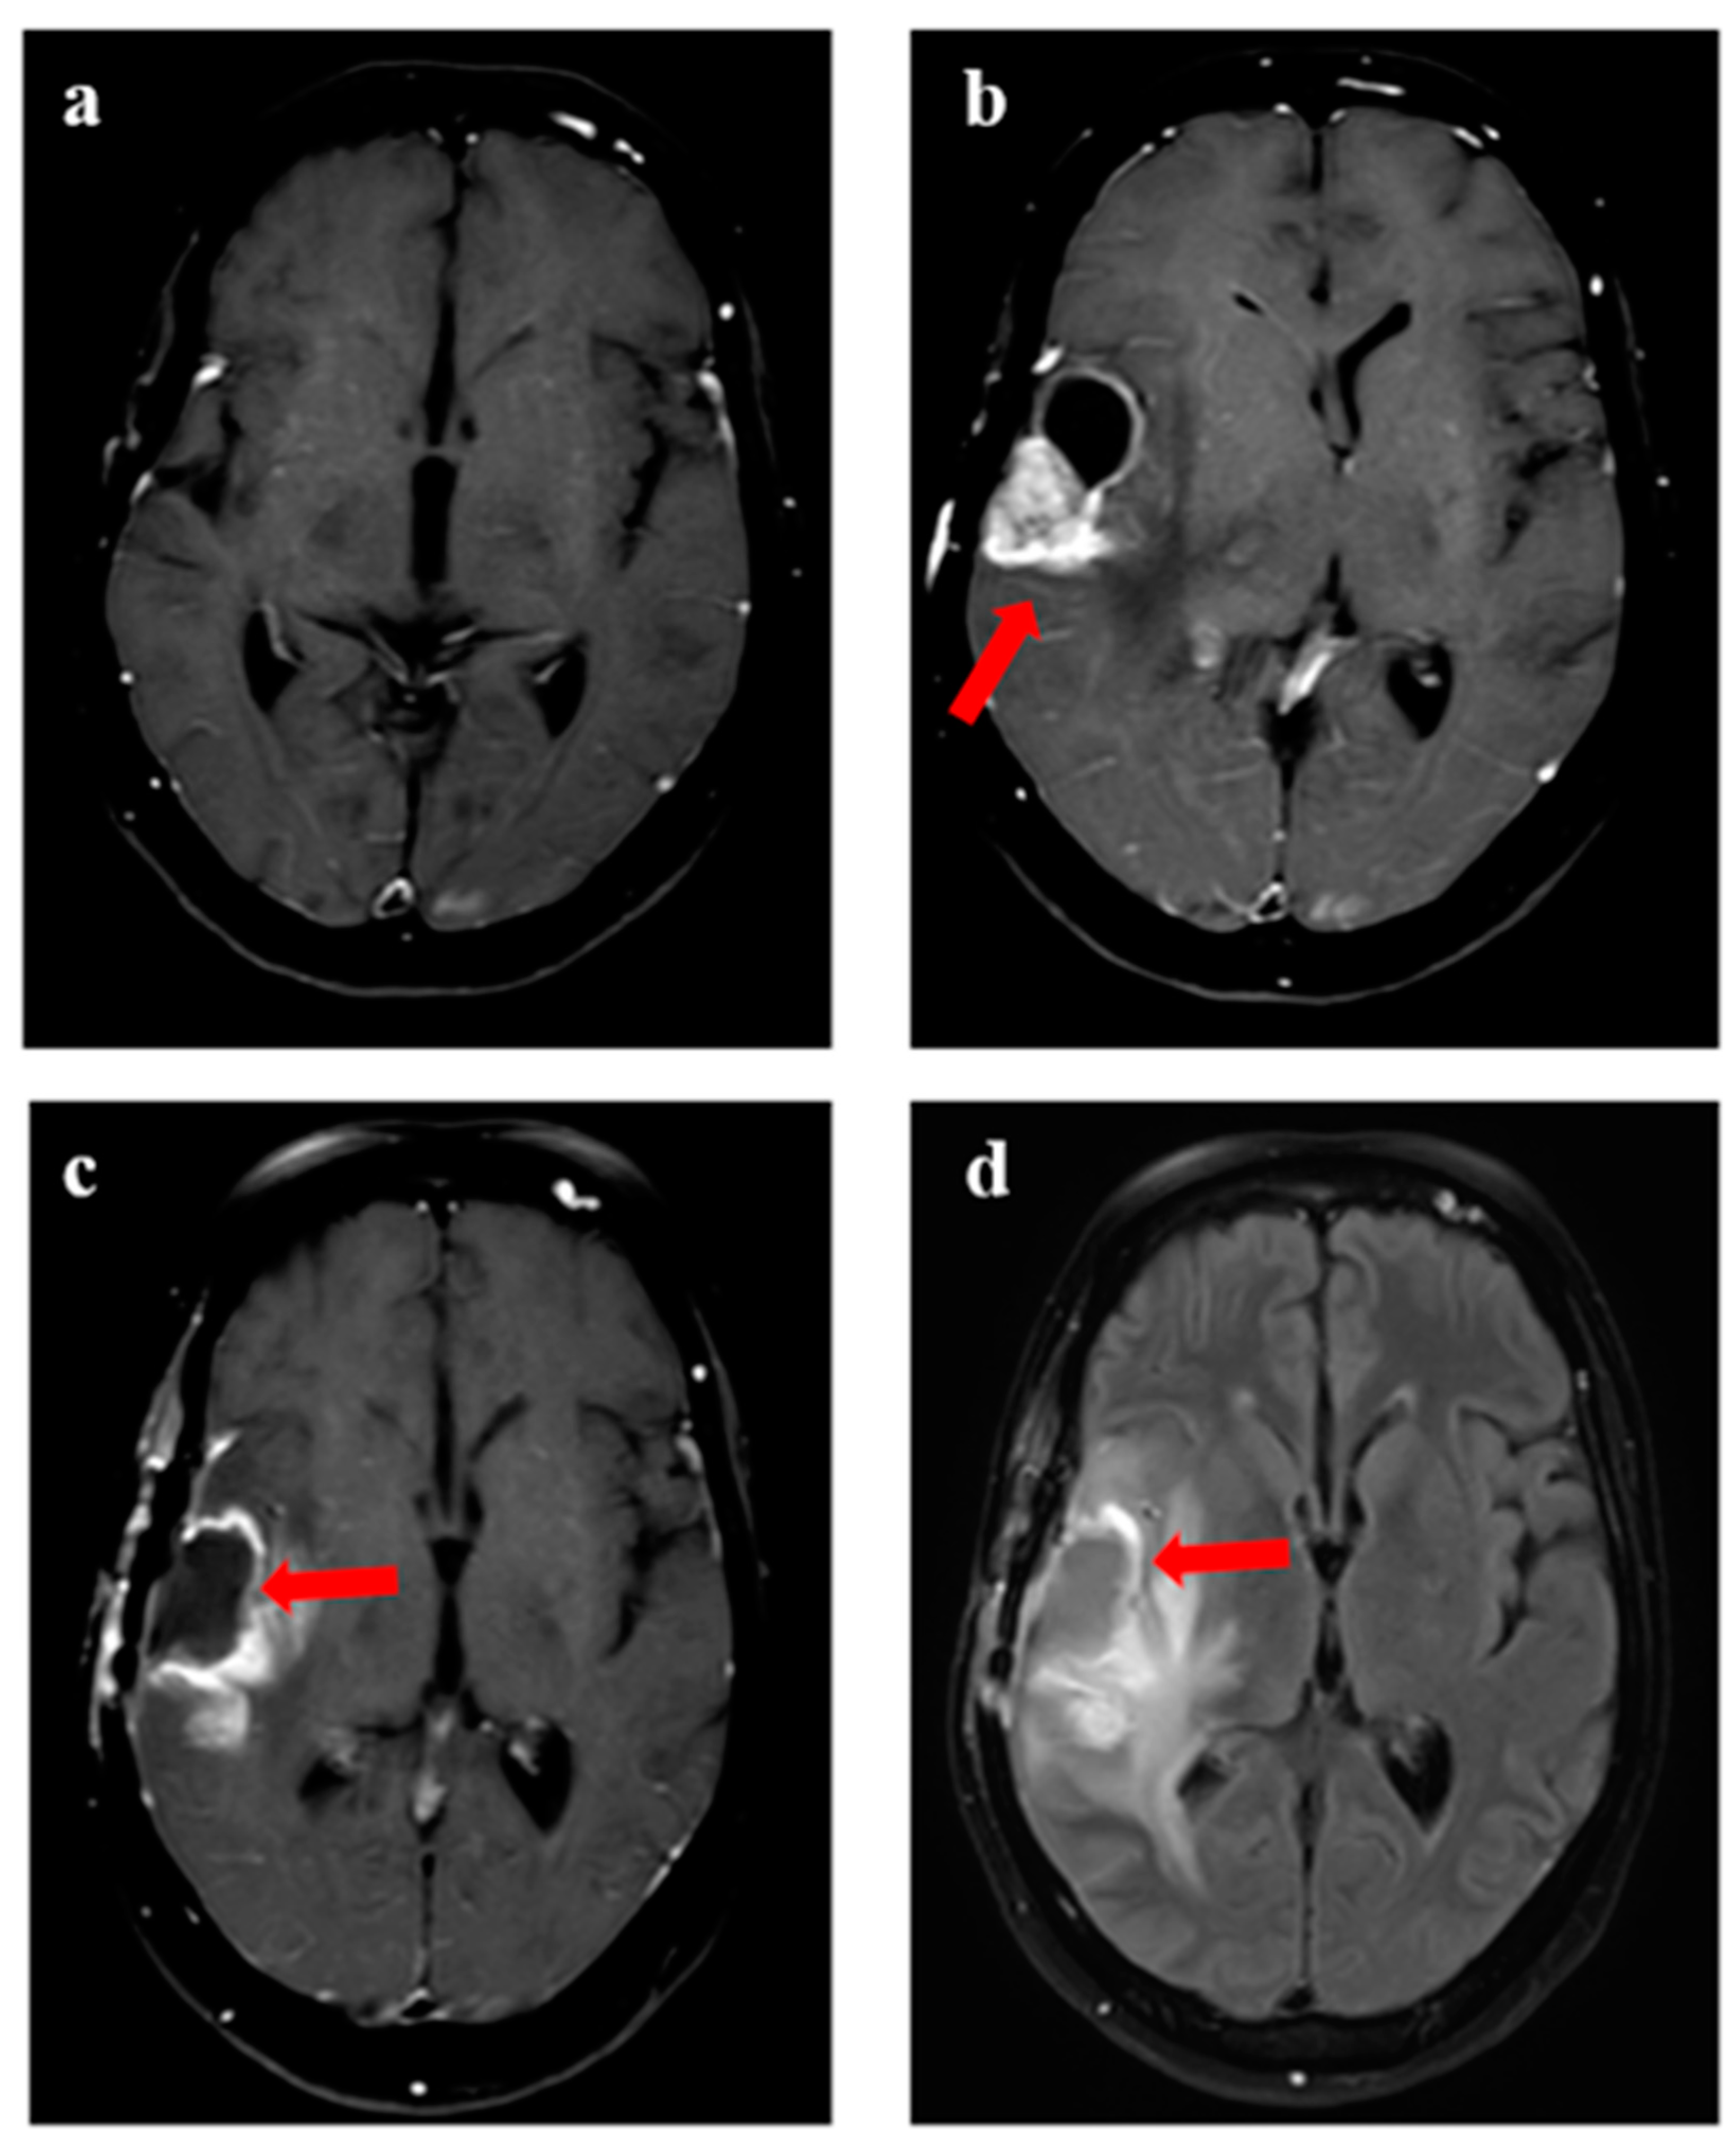

Figure 3.

Progression in a 47-year female with glioblastoma with MGMT gene promoter methylation. (a) shows T1w axial view following completion of adjuvant chemotherapy (after surgery and radiation), with (b) showing local recurrence after 2.5 years with enhancing component and cystic component (arrow). (c,d) represented the surgical cavity on T1w contrast and T2w FLAIR axial view when the patient was considered for reirradiation.

Figure 4.

Disease evolution from first progression to subsequent recurrence following re-irradiation in a 25-year female with IDH-mutant grade 3 astrocytoma. (a) shows T1w contrast-enhanced MRI with resection cavity over the right frontal region, with contrast-enhancing recurrent disease seen over the posterior aspect of the cavity (arrow) in (b). Subsequent imaging shows MRI following resection of the disease in (c), which was confirmed as recurrent HGG. (d) shows an enhancing area with central necrosis over the resected and re-irradiated region (8 months following ReRT) over the right frontal-parietal, which was not showing any metabolic uptake on corresponding PET imaging in (e). However, the other area of enhancing nodule over the left periventricular region shows high avidity, considered a distant recurrence. (f) shows MRI performed after 2 months, which confirmed new areas of distant disease, while the re-irradiated region (non-avid on PET) continued to be stable, confirming RT-related changes.